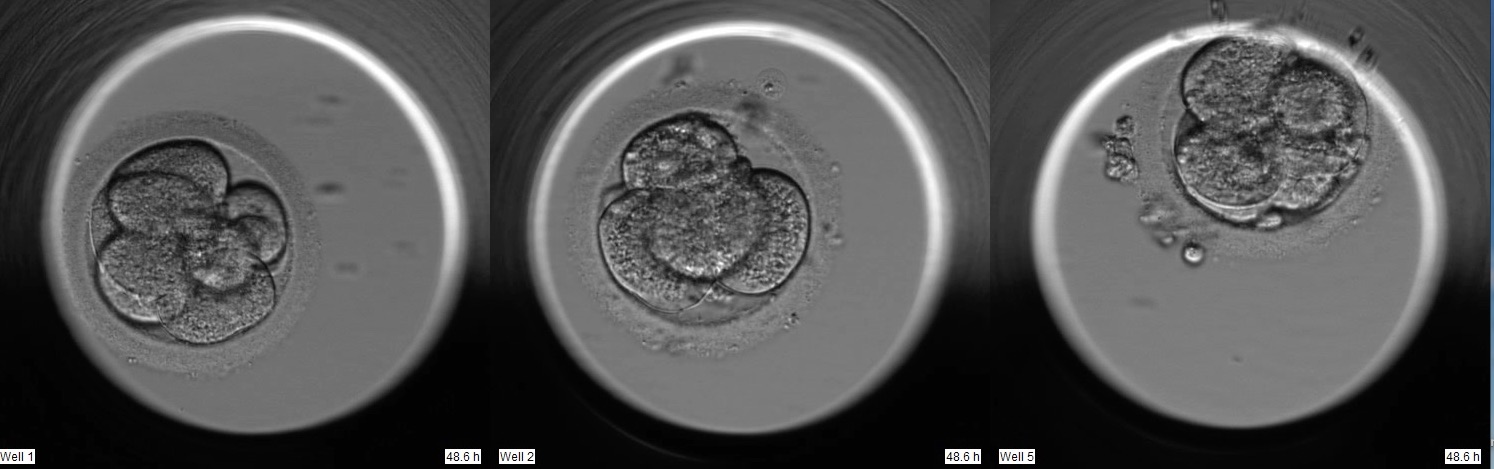

bitte um Beurteilung meiner drei verbleibenden Kryos. Die Linke und in der Mitte wurden an Tag 3 eingefroren als 8-Zeller. Die rechte wurde bis zur Blastozyste weiterentwickelt.

Ich habe drei Entwicklungsstadien aus dem Film abgebildet. 1. Foto 48 Stunden, 2. Foto 69 Stunden und letztes Bild nach 109 Stunden.

alle drei Embryonen haben an Tag 3 zeitgerechte und gute Strukturen

und somit ein gutes Potential, um zu entwicklungsfähigen BCs zu werden.